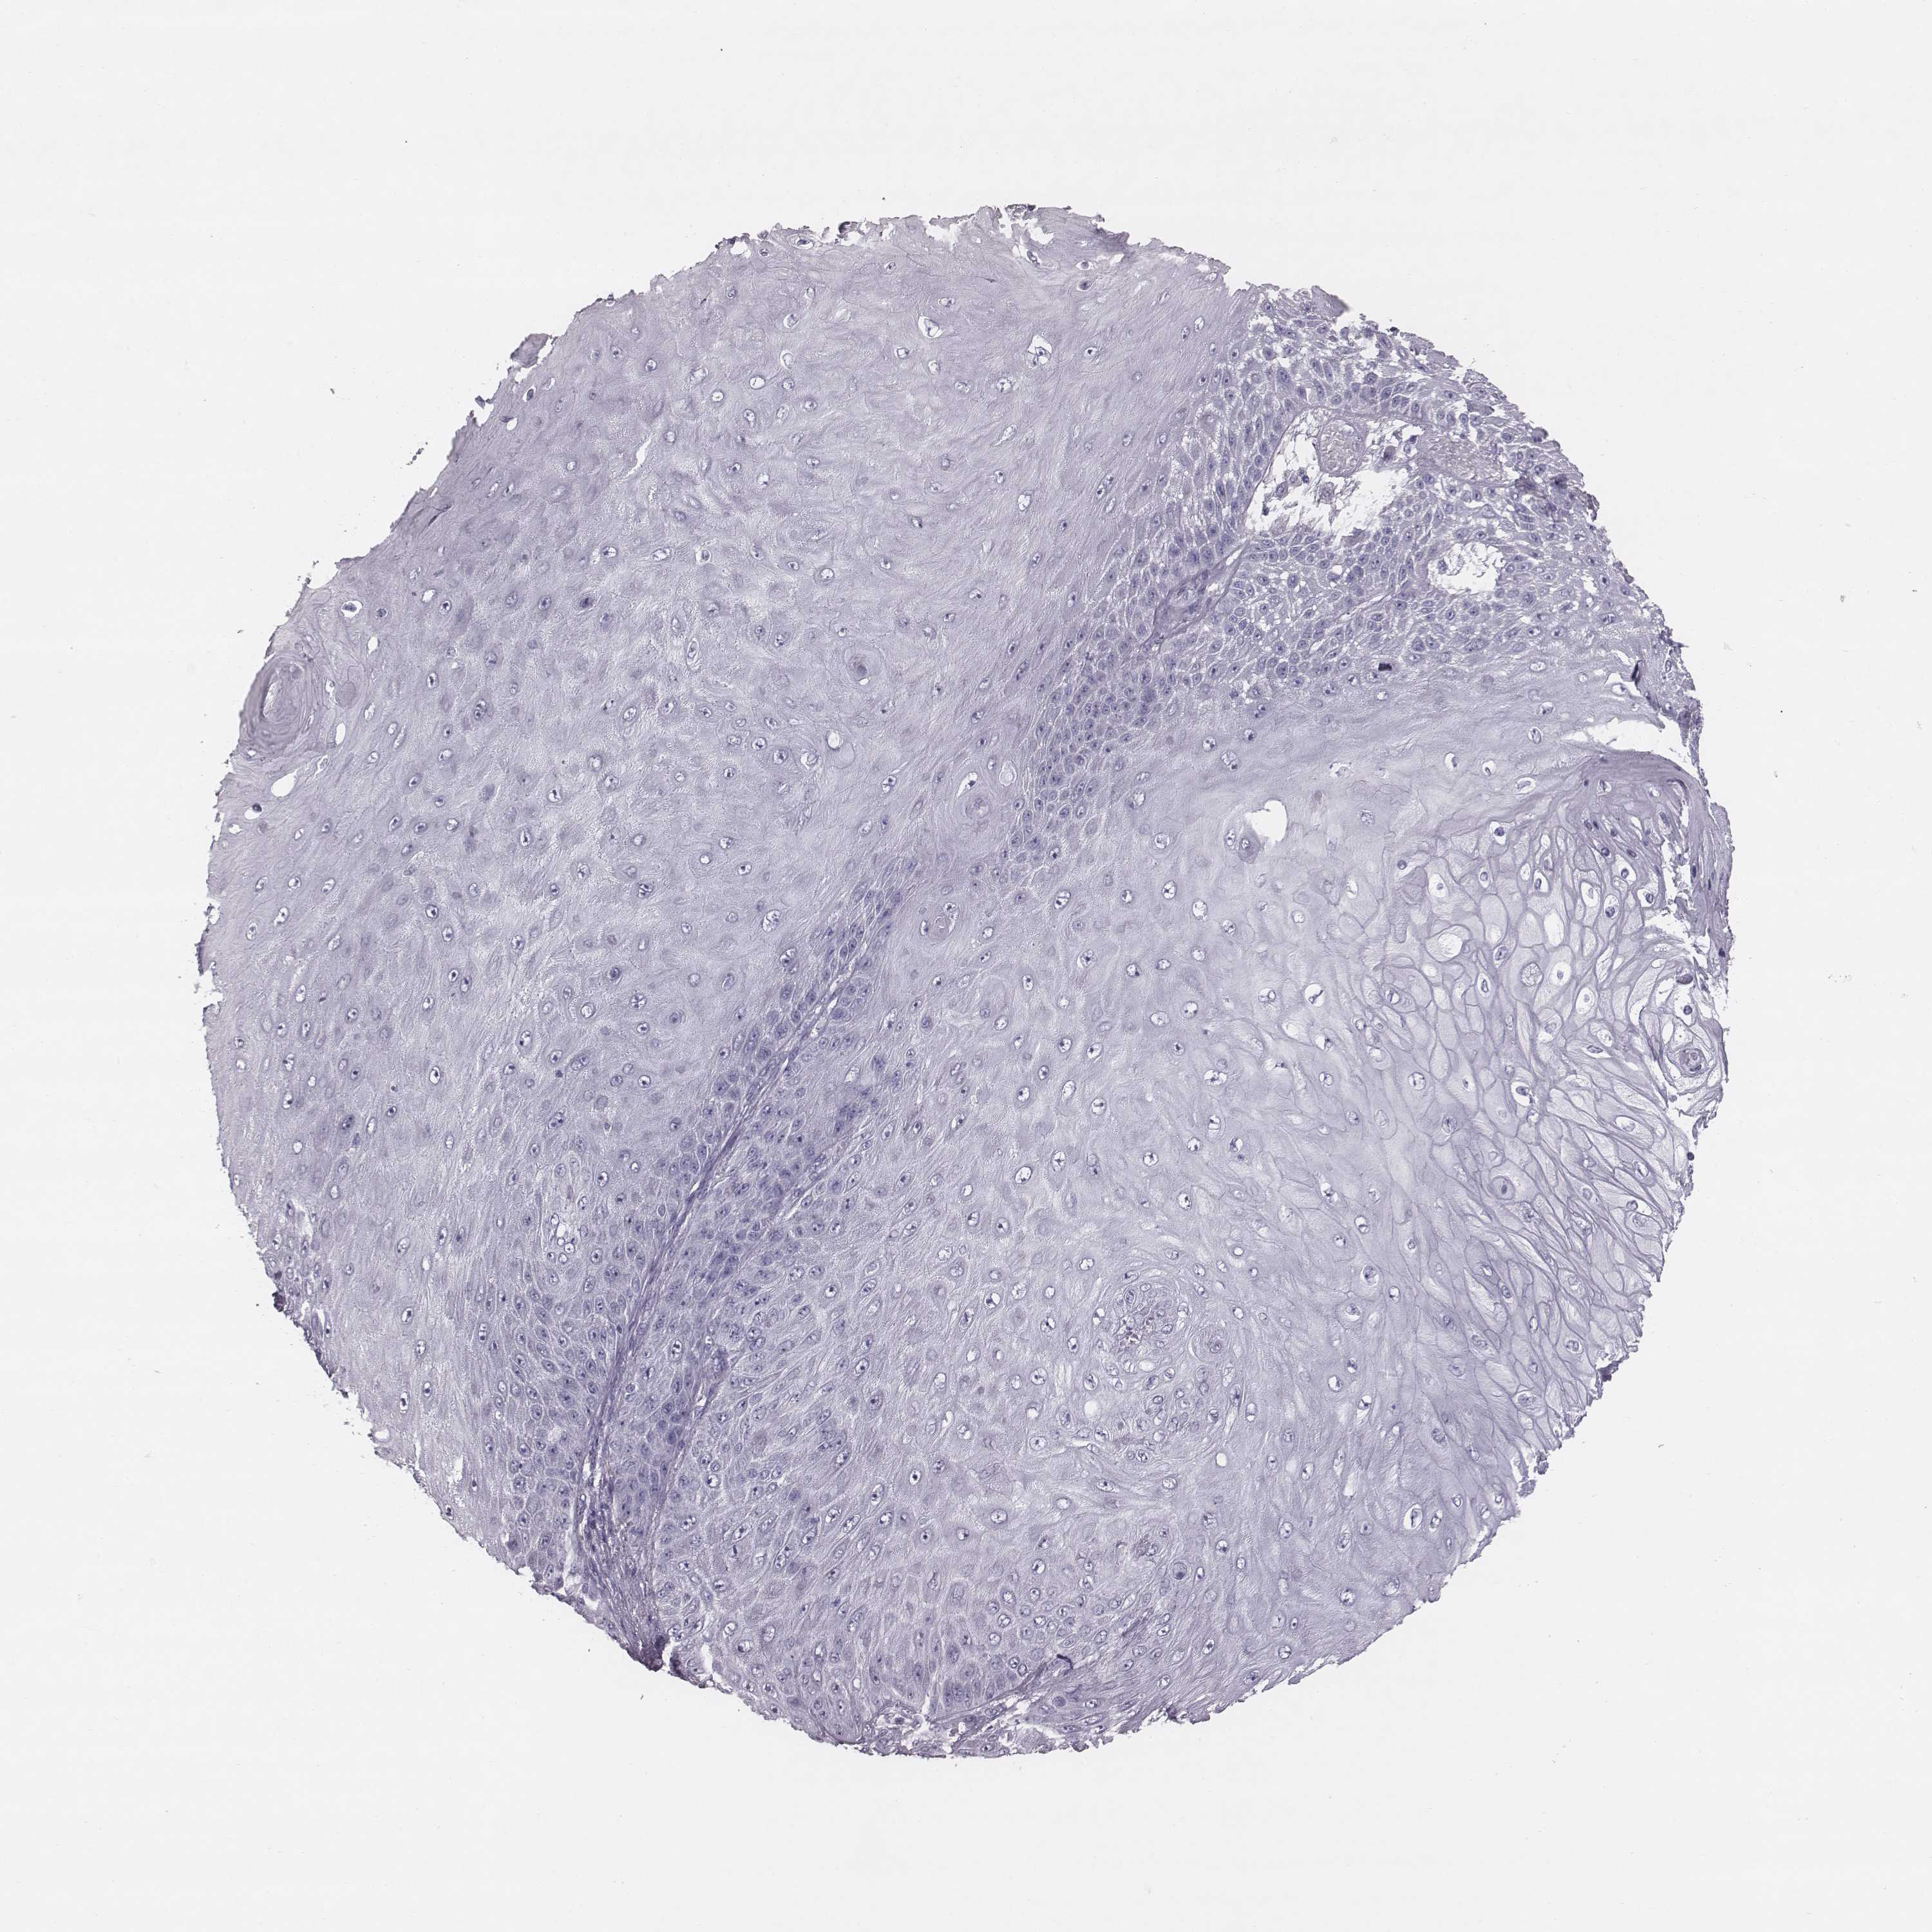

Basal cell and squamous cell cancer

SKIN CANCER - Protein expressioni

A mouse-over function shows sample information and annotation data. Click on an image to view it in a full screen mode. Samples can be filtered based on level of antibody staining by selecting one or several of the following categories: high, medium, low and not detected. The assay and annotation is described here.

Antibody stainingi

Antibody staining in the annotated cell types in the current human tissue is reported as not detected, low, medium, or high, based on conventional immunohistochemistry profiling in selected tissues. This score is based on the combination of the staining intensity and fraction of stained cells.

Each image is clickable and will lead to virtual microscopy that enables deeper exploration of all samples and also displays staining intensity scores, fraction scores and subcellular localization as well as patient and tissue information for each sample.

Antibody HPA036912

Staining

High

Strong

Quantity

Location

Squamous cell carcinoma, NOS